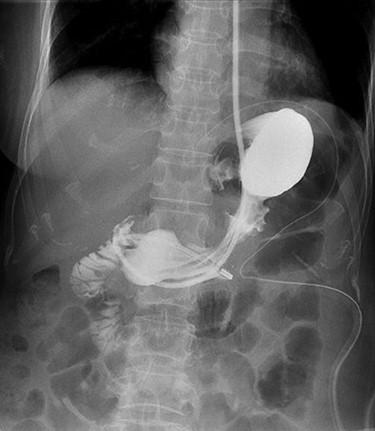

A 56-year-old lady presented with per rectal bleeding and 4 kg weight lost over 1 month. Oesophagogastroduodenoscopy (OGD) performed revealed a large gastric submucosal tumour over the lesser curve (Fig. 1). The proximal margin of the tumour is <1 cm from the GEJ, whereas the distal margin is in the mid lesser curve, about 5 cm proximal to the incisura. Endoscopic ultrasound with fine-needle aspiration performed confirmed the submucosal tumour to be GIST.

Computed tomography thorax abdomen pelvis performed showed a 4.2 × 8.0 × 5.3 cm transmural mass with prominent luminal and exophytic components at the gastric cardia and GEJ (Fig. 2). There were otherwise no enlarged lymph nodes or distant metastases.